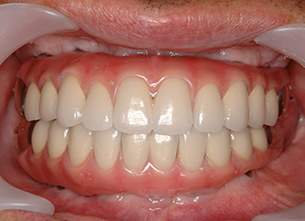

症例1 : 上下顎無菌顎症例

69歳、男性。

• 上顎は両側サイナスリフトと同時に即時荷重を行った。

• 下顎は抜歯即時埋入即時荷重を行った。

• 最終補綴物は、チタンのP.I.B.とM.B.のコンビネーションで修復した。

• 本症例の要旨は第39回日本口腔インプラント学会(大阪)にて症例報告した。